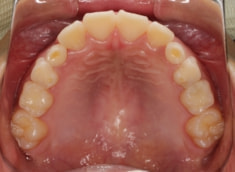

症例紹介

小児期ケース:叢生(ガタガタ)

治療法:拡大プレート+フルパッシブブラケット(クリアスナップ)

治療後(1年1ヶ月後)